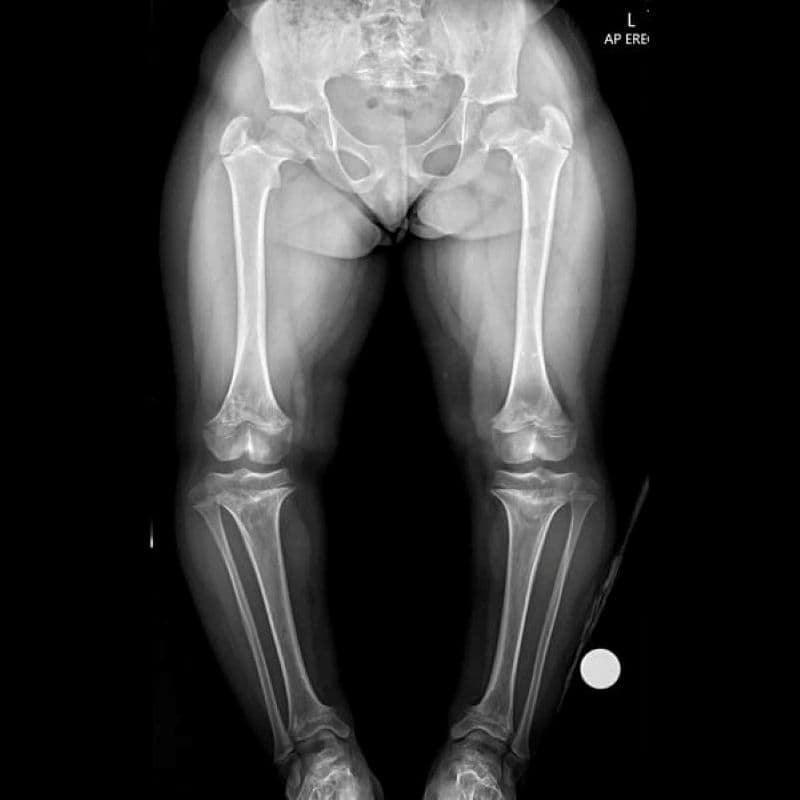

- Chẩn đoán hình ảnh: Chụp X-quang các vùng xương như chân, tay, đùi, sọ để phát hiện đặc điểm điển hình của bệnh.